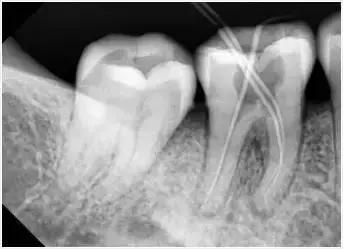

应用平行投照X光方法、根管长度测量仪确定根管长度,较 好插针拍X片。

封闭整个根管系统、堵塞主根管和侧副根管出口、防止微生物和液体的渗漏。无论是侧方加压法还是垂直加压法,应做到根管充填致密,根管充填后X光片上无根管腔隙,也不能超出根尖孔。